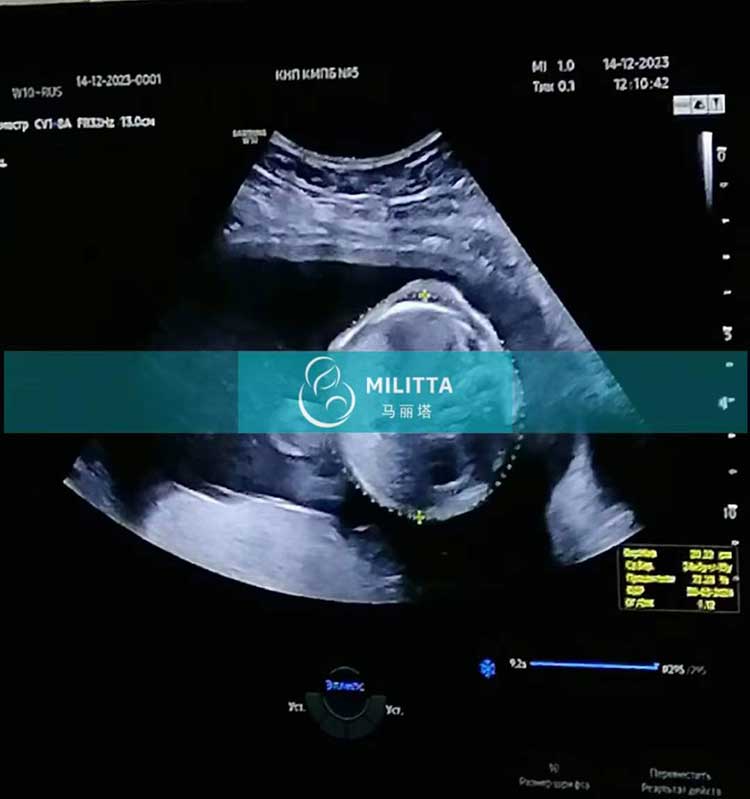

乌克兰试管妈妈做四维彩超检查看到活泼好动的小宝贝

陪同这位乌克兰试管妈妈来医院做四维彩超检查,彩超下清楚看到了我们活泼好动的小宝贝,太可爱啦